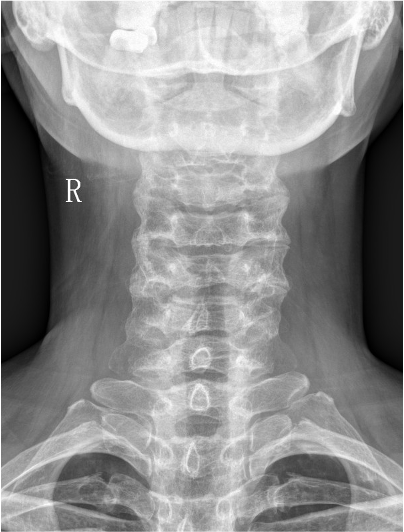

【影像】X线片见颈椎侧弯,右侧侧块小。

【诊断】寰枢关节半脱位(顺时针旋转);颈源性头痛;颈源性失眠;